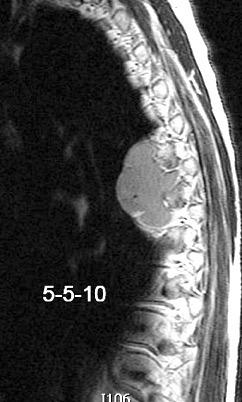

32 años .Preeclampsia a los 19. Hipertensión no controlada. Masa paravertebral sólida que se realza intensamente con afectación ósea.

Yue Y t al. Asymptomatic left posterior mediastinal functional Paraganglioma. A case report. Medicine . 2019